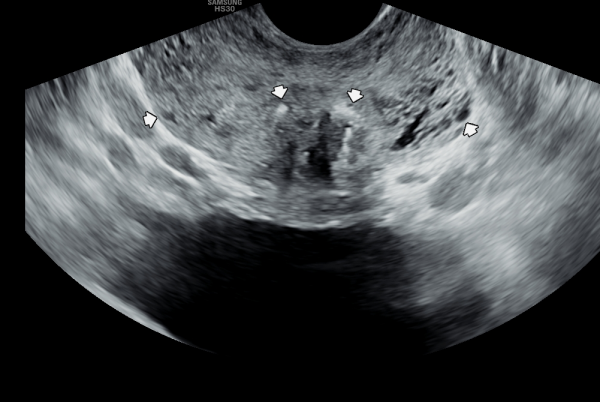

5년전 내원 당일 검사한 경직장 전립선 초음파 사진상 좌우 사정관 입구의 막혀있는 미세 결석들과 전립선관의 순환장애로 전립선의 낭종들이 관찰되는 사진입니다.

A transrectal prostate ultrasound image taken on the day of the initial visit five years ago shows microcalcifications blocking the openings of both ejaculatory ducts, as well as prostatic cysts caused by impaired circulation in the prostatic ducts.